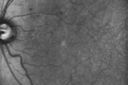

Diabetic Macular Ischemia - Enlarged FAZ - OCT-A447 views70 year old female diagnosed with diabetes 2 years ago. Her blood pressure was normal at 116/73. She has vision loss for 6 months in both eyes. VA is 20/100 OU. OCT-A shows macular ischemia.

Diabetic Macular Ischemia - Enlarged FAZ - OCT-A432 views70 year old female diagnosed with diabetes 2 years ago. Her blood pressure was normal at 116/73. She has vision loss for 6 months in both eyes. VA is 20/100 OU. OCT-A shows macular ischemia.

Diabetic Macular Ischemia - Enlarged FAZ - OCT-A426 views70 year old female diagnosed with diabetes 2 years ago. Her blood pressure was normal at 116/73. She has vision loss for 6 months in both eyes. VA is 20/100 OU. OCT-A shows macular ischemia.

Diabetic Macular Ischemia - Enlarged FAZ - OCT-A395 views70 year old female diagnosed with diabetes 2 years ago. Her blood pressure was normal at 116/73. She has vision loss for 6 months in both eyes. VA is 20/100 OU. OCT-A shows macular ischemia.